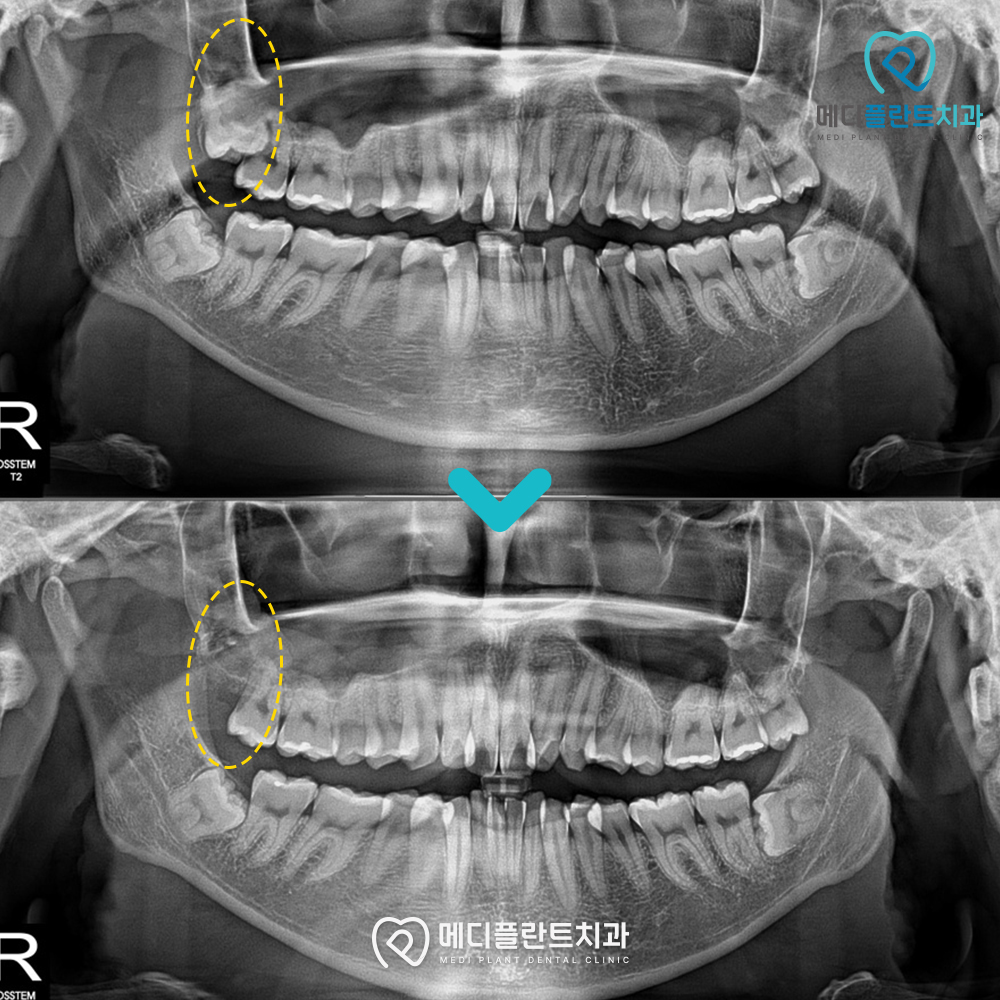

검진 시 촬영한 파노라마 엑스레이를 보면

노란 점선 부분의 사랑니가 정상적으로 나오지 못하고

옆으로 누워 있는 모습이 확인됩니다.

시술 과정에서는 매복 정도와 치아 위치를 고려해

사랑니를 분리하여 안정적으로 제거하였습니다.

시술 후 엑스레이를 보면 사랑니가 제거되고

주변 치아와 잇몸 구조에 문제 없이

안정화된 모습이 확인됩니다.